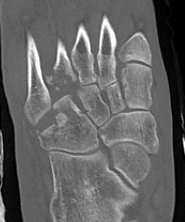

CT

cubcubcub